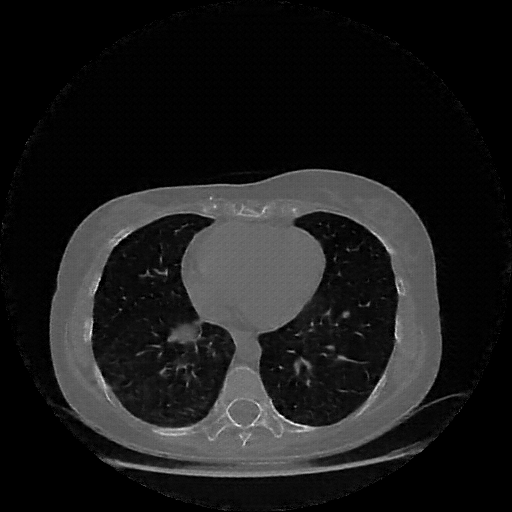

Targeted Slice 70 - Lung Window Analysis (Generated vs Real Venous)

0.720

Lung SSIM

114.8

Lung RMSE

45.1

Lung MAE

Average Lung Window Metrics Across All Slices (103 slices) - Generated vs Real Venous

0.735

Lung SSIM (Avg)

109.1

Lung RMSE (Avg)

41.9

Lung MAE (Avg)

Original NATIVE CT scan (input)

Lung window (WL -600, WW 1500 β†’ Low βˆ’1350, High +150)